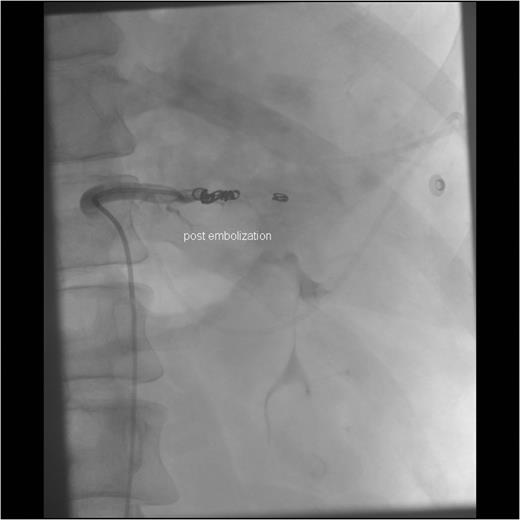

After the CT study, angiographic embolization of the splenic artery was performed. Angiographic catheter was inserted through the right femoral artery and guided into the splenic artery through the celiac trunk. The Spongostan (Ethicon Inc., Somerville, NJ, USA) particles were deployed to the branches of the splenic artery as the contrast leakage was seen in multiple locations. The proximal SAE with three Gianturco coils (Cook Medical Inc., Bloomington, IN, USA) and one Azur Peripheral HydroCoil (Terumo Medical Corporation, Somerset, NJ, USA) were deployed 4 cm distal to the celiac trunk (Figs 3 and 4). After the procedure, the patient was admitted to intensive care unit.

Angiographic imaging post-embolization observing four proximal coils in the splenic artery 3–4 cm distal to the celiac trunk.